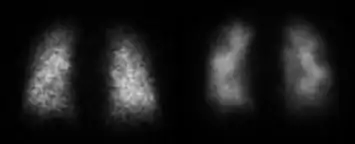

![]() Normal pulmonary ventilation and perfusion (V/Q) scan. The nuclear medicine V/Q scan is useful in the evaluation of pulmonary embolism. | |